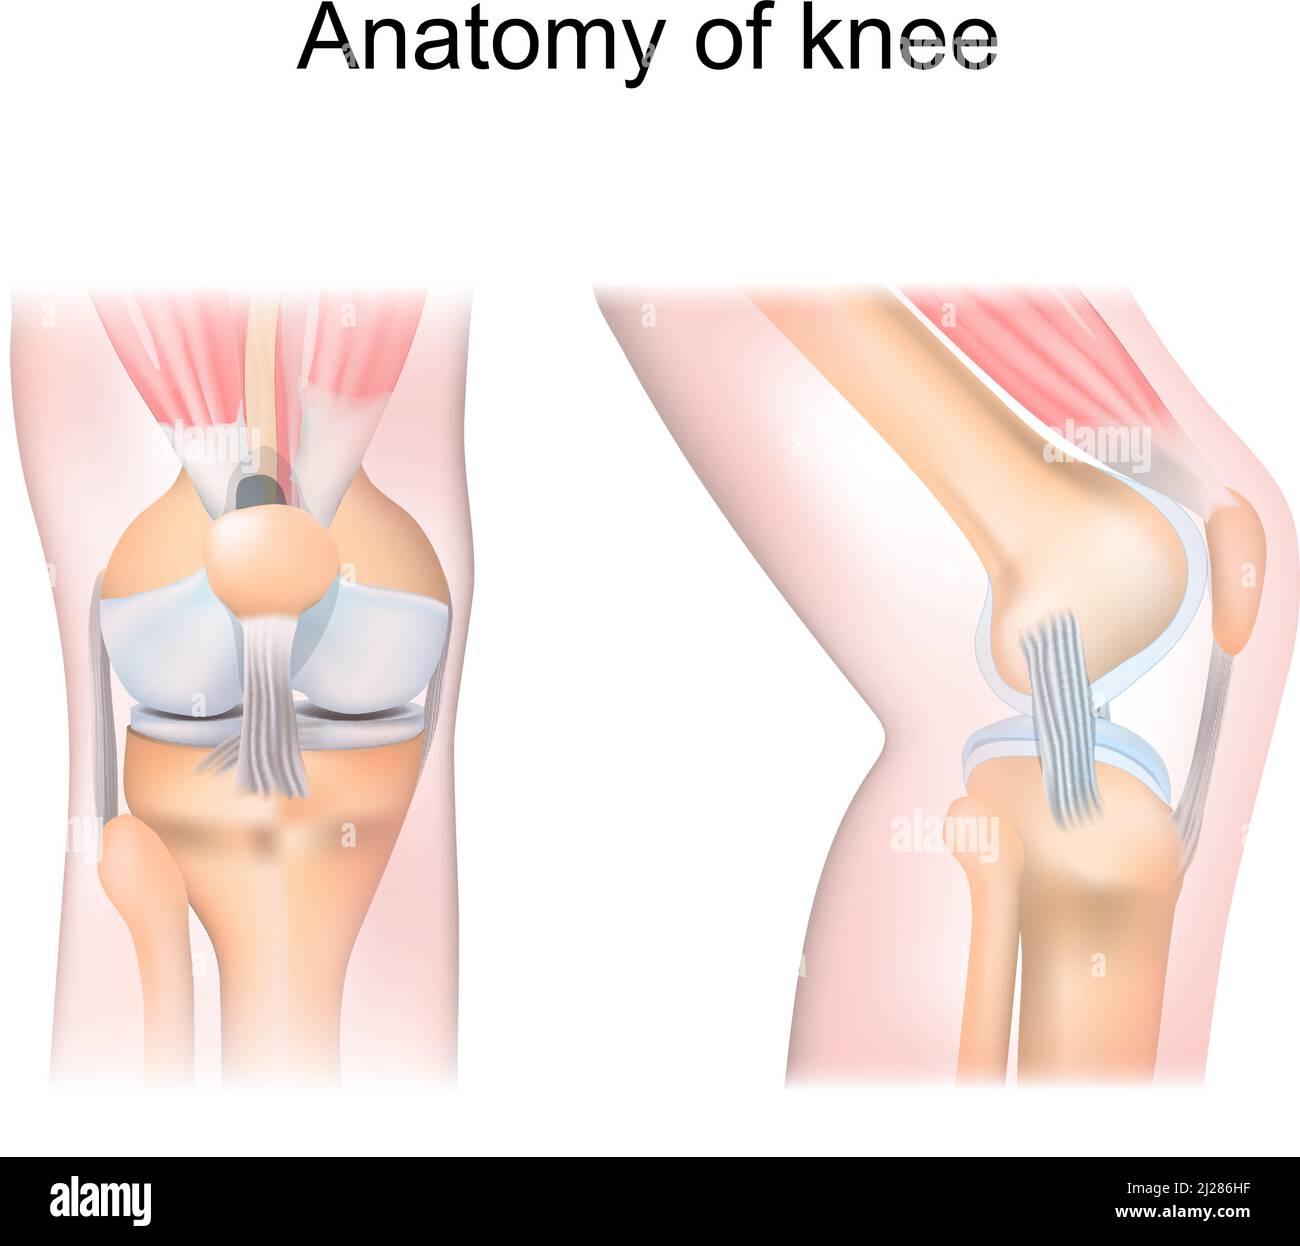

knee anatomy. side and front view. Cross section of the joint showing the main parts: femur, fibula, articular capsule, menisci, muscles and ligaments Stock Vectorhttps://www.alamy.com/image-license-details/?v=1https://www.alamy.com/knee-anatomy-side-and-front-view-cross-section-of-the-joint-showing-the-main-parts-femur-fibula-articular-capsule-menisci-muscles-and-ligaments-image466090059.html

knee anatomy. side and front view. Cross section of the joint showing the main parts: femur, fibula, articular capsule, menisci, muscles and ligaments Stock Vectorhttps://www.alamy.com/image-license-details/?v=1https://www.alamy.com/knee-anatomy-side-and-front-view-cross-section-of-the-joint-showing-the-main-parts-femur-fibula-articular-capsule-menisci-muscles-and-ligaments-image466090059.htmlRF2J286HF–knee anatomy. side and front view. Cross section of the joint showing the main parts: femur, fibula, articular capsule, menisci, muscles and ligaments